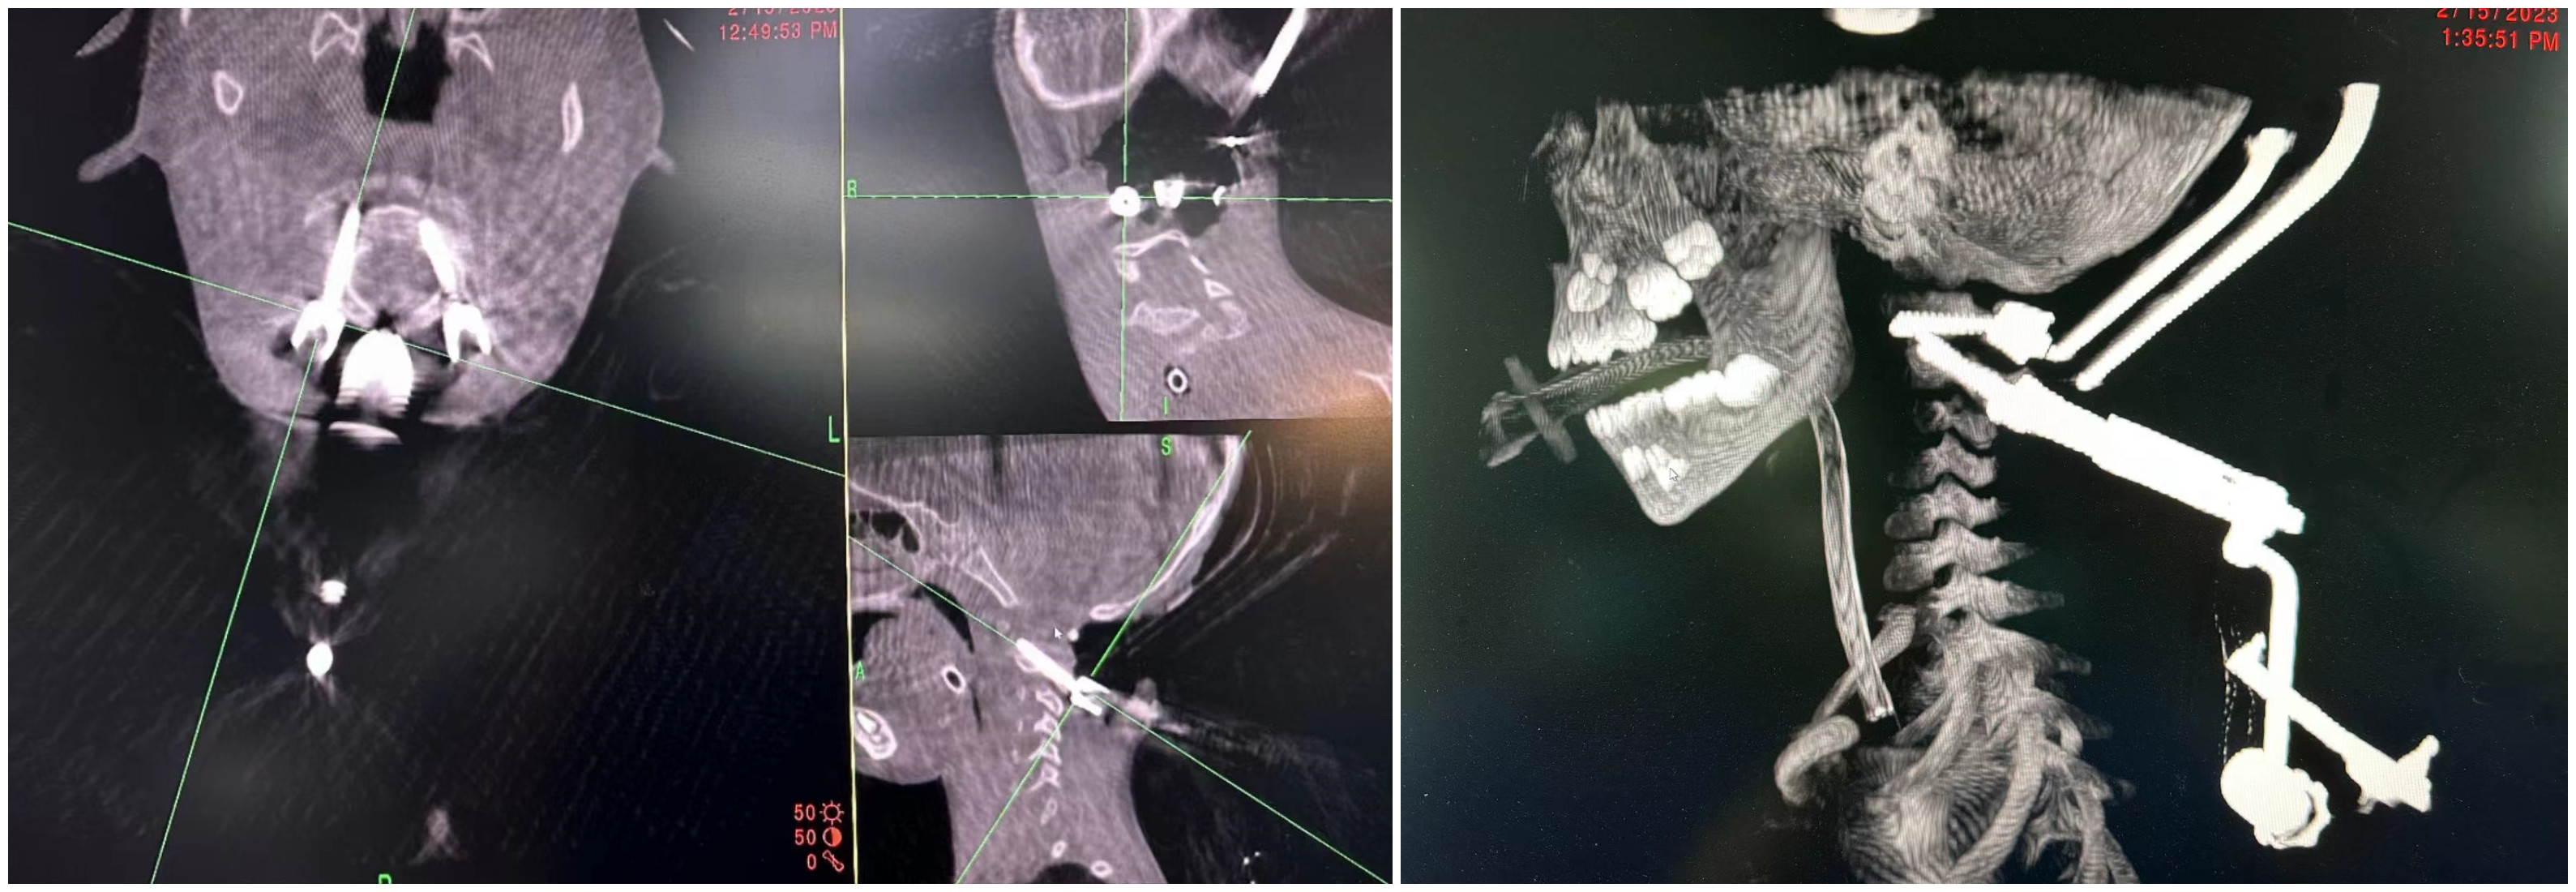

患儿术中资料

这是甘肃省首次使用“O”型臂导航系统实施脊柱手术,本例手术的成功实施使医院在骨科复杂及高难度手术方面取得了进展,进一步推动脊椎手术向微创化、精准化、智能化方向发展。

“O”型臂导航系统是全球最为先进的导航精准手术平台,由“O”型臂手术图像系统和全球最先进的Stealth Station S8手术导航系统组成。在这一系统辅助下,可使医生手术视角更广、判读脊柱状况更精确,可准确避开重要的血管、神经,使置入椎弓根螺钉的准确度更高,提高了手术的安全性,缩短了手术时间,加快了患者康复。